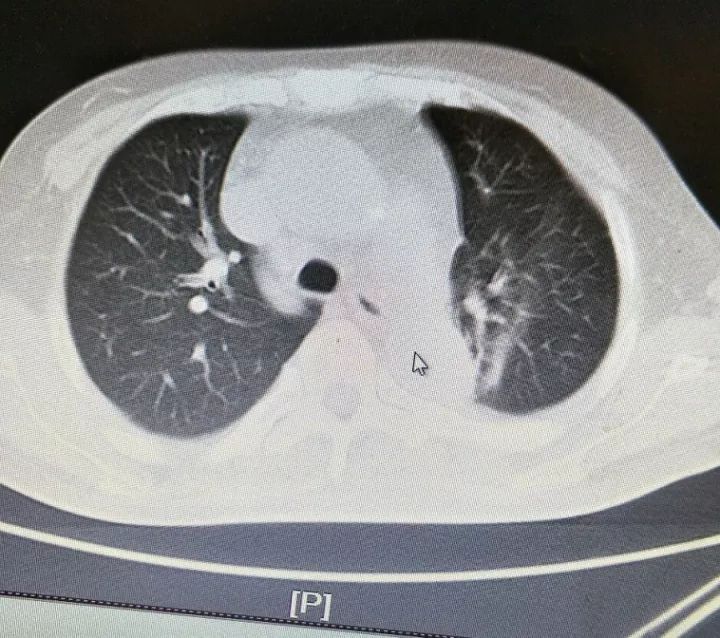

患者入院第2天,行床旁血液透析,共脱水3000ml,诉胸痛症状稍缓解。复查心梗二项:肌钙蛋白T 1.46 ng/ml,肌红蛋白 1313 ng/ml;BNP>35000 pg/ml;肾功:尿素氮21.07mmol/L,肌酐498umol/L;心脏彩超:左房、左室增大,左室壁运动幅度普遍行减低,肺动脉压增高,各瓣膜反流;射血分数36%;胸部CT如下图。